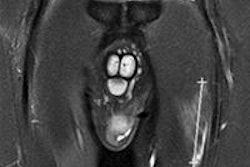

A 28-year-old male volleyball player with a finger injury. Consecutive axial fat-suppressed T2-weighted MR images of the third finger: (A) Proximally, there is normal appearance of the distal extensor tendon (short arrows); (B) Distally to A, the distal extensor tendon is thickened with increased signal intensity (arrows); (C) More distally to B, the distal extensor tendon is no longer depicted (*), consistent with a complete distal rupture. (D) Sagittal fat-suppressed T2-weighted MR image of the third finger depicts the complete rupture of the distal extensor tendon (arrow). The associated impaction fracture and bony contusions about the distal interphalangeal joint also are seen. Image courtesy of Dr. Daichi Hayashi, PhD.Recent studies show the incidence of volleyball-related injuries is between 1.7 and 3.0 injuries per 1,000 hours of play, and many injuries occur due to repetitive jumping and hitting the ball overhead, he pointed out. Most injuries occur among players in front-line positions, which is where jumping and landing occur most often. Most injuries involve the lower extremities, and match injuries are more frequent than training injuries.